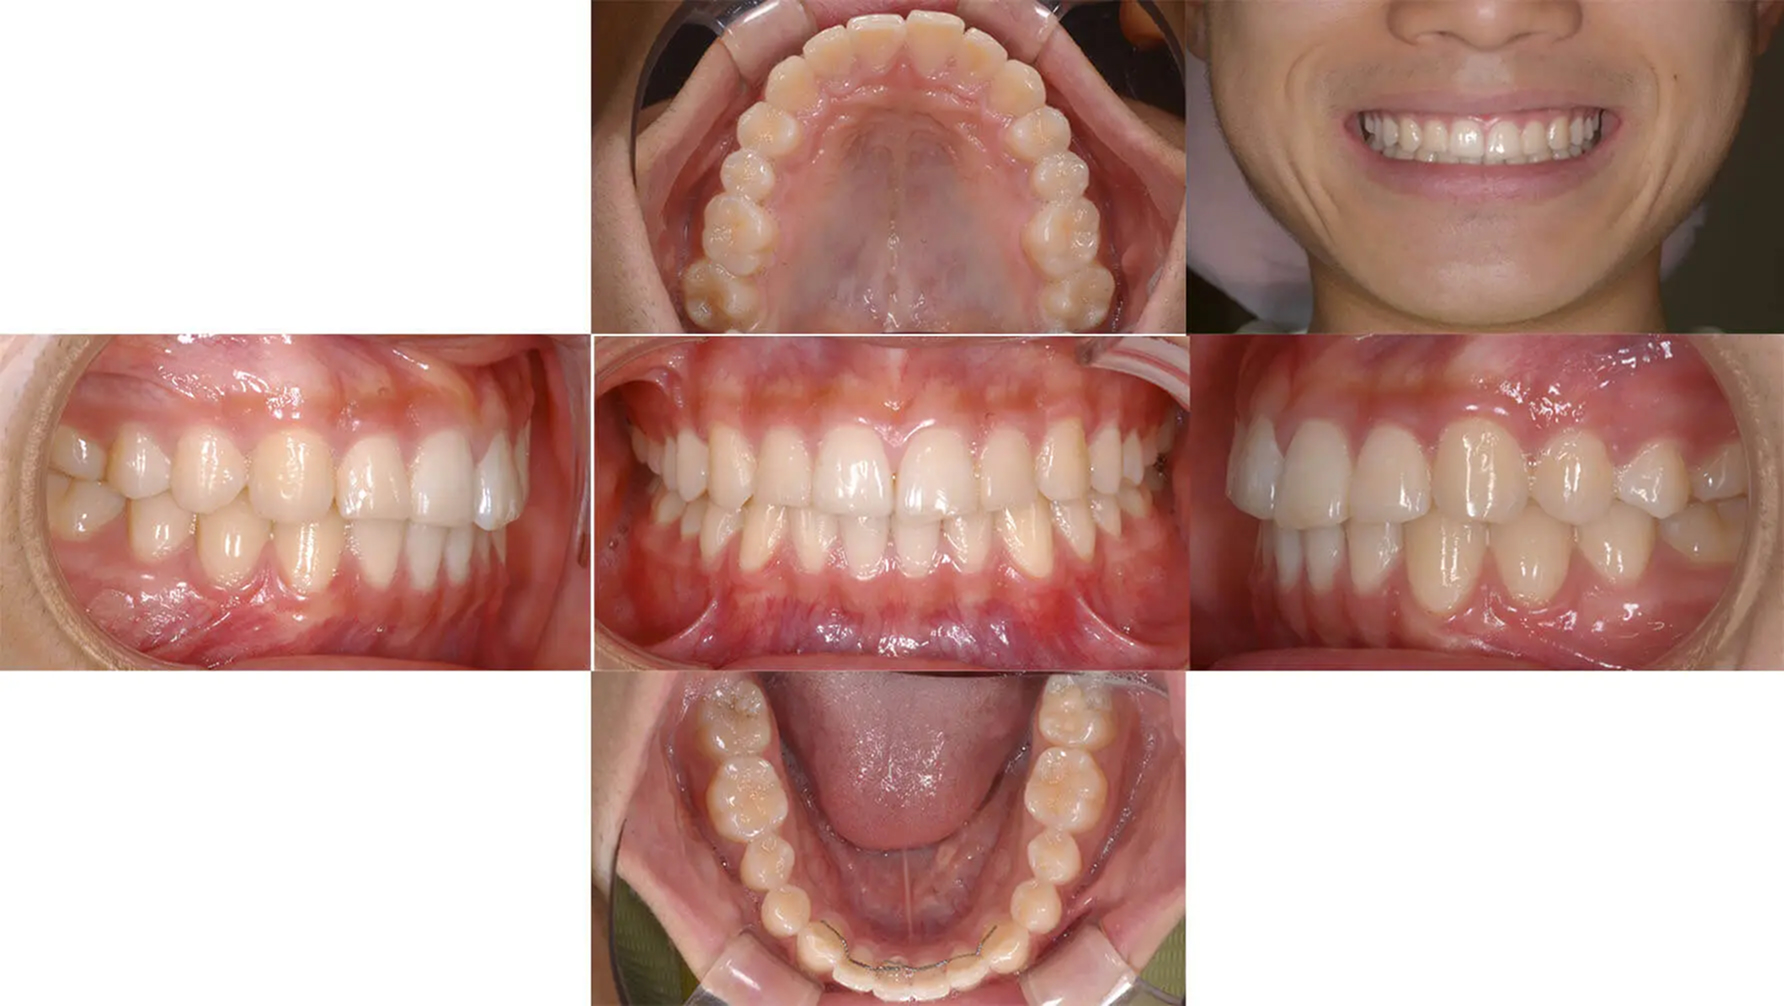

Case03顔の中心のズレを改善した症例

歯が顔とズレているの気になると来院した中学生です。左上の八重歯も改善希望でした。診査の結果、矯正用アンカーを用いることで抜歯なし行えると診断しました。8か月と短期間で終えることができました。八重歯の部分は後戻りしやすいので、保定装置の装着が必須になります。

初診 2017.8.22

矯正治療開始 2017.9.13

ファイナル 2018.5.1

| 主訴 | 顔の中心と歯の真ん中がずれている |

| 診断 | 両側アングル1級の叢生 |

| 矯正方法 | 矯正用アンカーを用いたマルチブラケット |

| 矯正期間 | 8か月・10回 |

| 費用 | 730,000円(税別) |

| 調整料 | 月1回 5,000円(税別) |